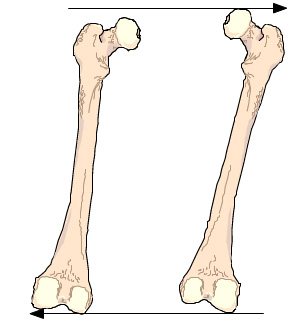

Leider werden seit über 100 Jahren Bein-Längen-Abweichungen im unbelasteten Zustand vermessen und auch so bebildert, ohne Kenntnis der 9 unterschiedlichen Ausweichhaltungen aus der Körper-Statischen-Mittellinie.

Dadurch werden diese Ausweichhaltungen der Fehlstatik (Winkel Verschiebungen, Rotation, Höhen-Abweichungen, Beinstellungs-Veränderungen) als Beinlängen-Abweichungen vermessen, die in über 99,…% effektiv nicht vorhanden sind.

1. Verschiebt sich das Becken zur Seite, oder verdreht es dasselbe, führt dies automatisch zu einer Beckenhöhenabweichung, die dann irrtümlich als Beinlängen-Unterschied bebildert und vermessen wird. |

Diese seitliche Verschiebung hat zur Folge, dass der Schenkel mit dem vergrösserten Winkel zum Becken nach innen drückt. Die Gegenseite drückt durch den kleineren Winkel die Hüftkugel noch oben. Dem wird dann vielmals durch auswärtsdrehen dieses Fusses dagegengehalten. | Beinstellungsveränderung Durch seitliche Hüftverschiebung, hier auf der Abbildung Mitte zu sehen ist, erfolgt eine scheinbare wie auch messbare längen Abweichungen. Grund dafür ist die seitliche Beckenverschiebung die zu einer Schenkel Winkel Veränderung zum Becken führt und somit den scheinbare längen Unterschied verursacht. |